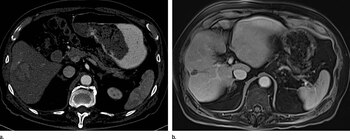

“El hepatocarcinoma celular es el subtipo de cáncer hepático más frecuente, dado que representa alrededor del 90% del total de casos. Con frecuencia, este cáncer no genera síntomas hasta etapas avanzadas, aunque hay quienes podrían experimentar dolor o sensibilidad abdominal, sangrados o hematomas, aumento de volumen abdominal, incremento o pérdida de peso sin explicación e ictericia (piel amarillenta)”, explicó Aballay Soteras.